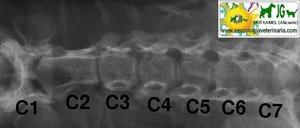

Radiografía columna cervical canina. Proyección latero-lateral |

Radiografía columna cervical canina. Proyección ventrodorsal |